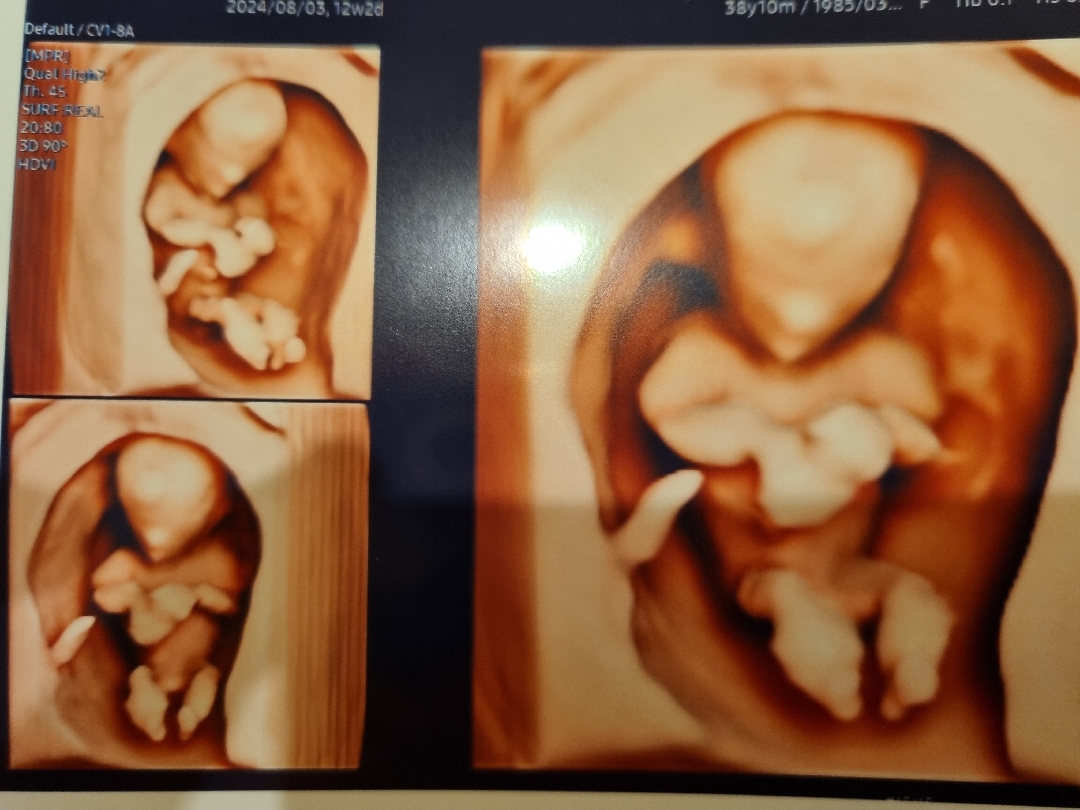

입체초음파♡

12주2일차 입체초음파 보고와서 열심히 자라준 아가에게 고맙고 감격이네요♡ 아들 딸 상관없이 건강하게만 자라주길 바래요^^ 소중한 생명을 품고계신 모든분들 파이팅 입니다!!